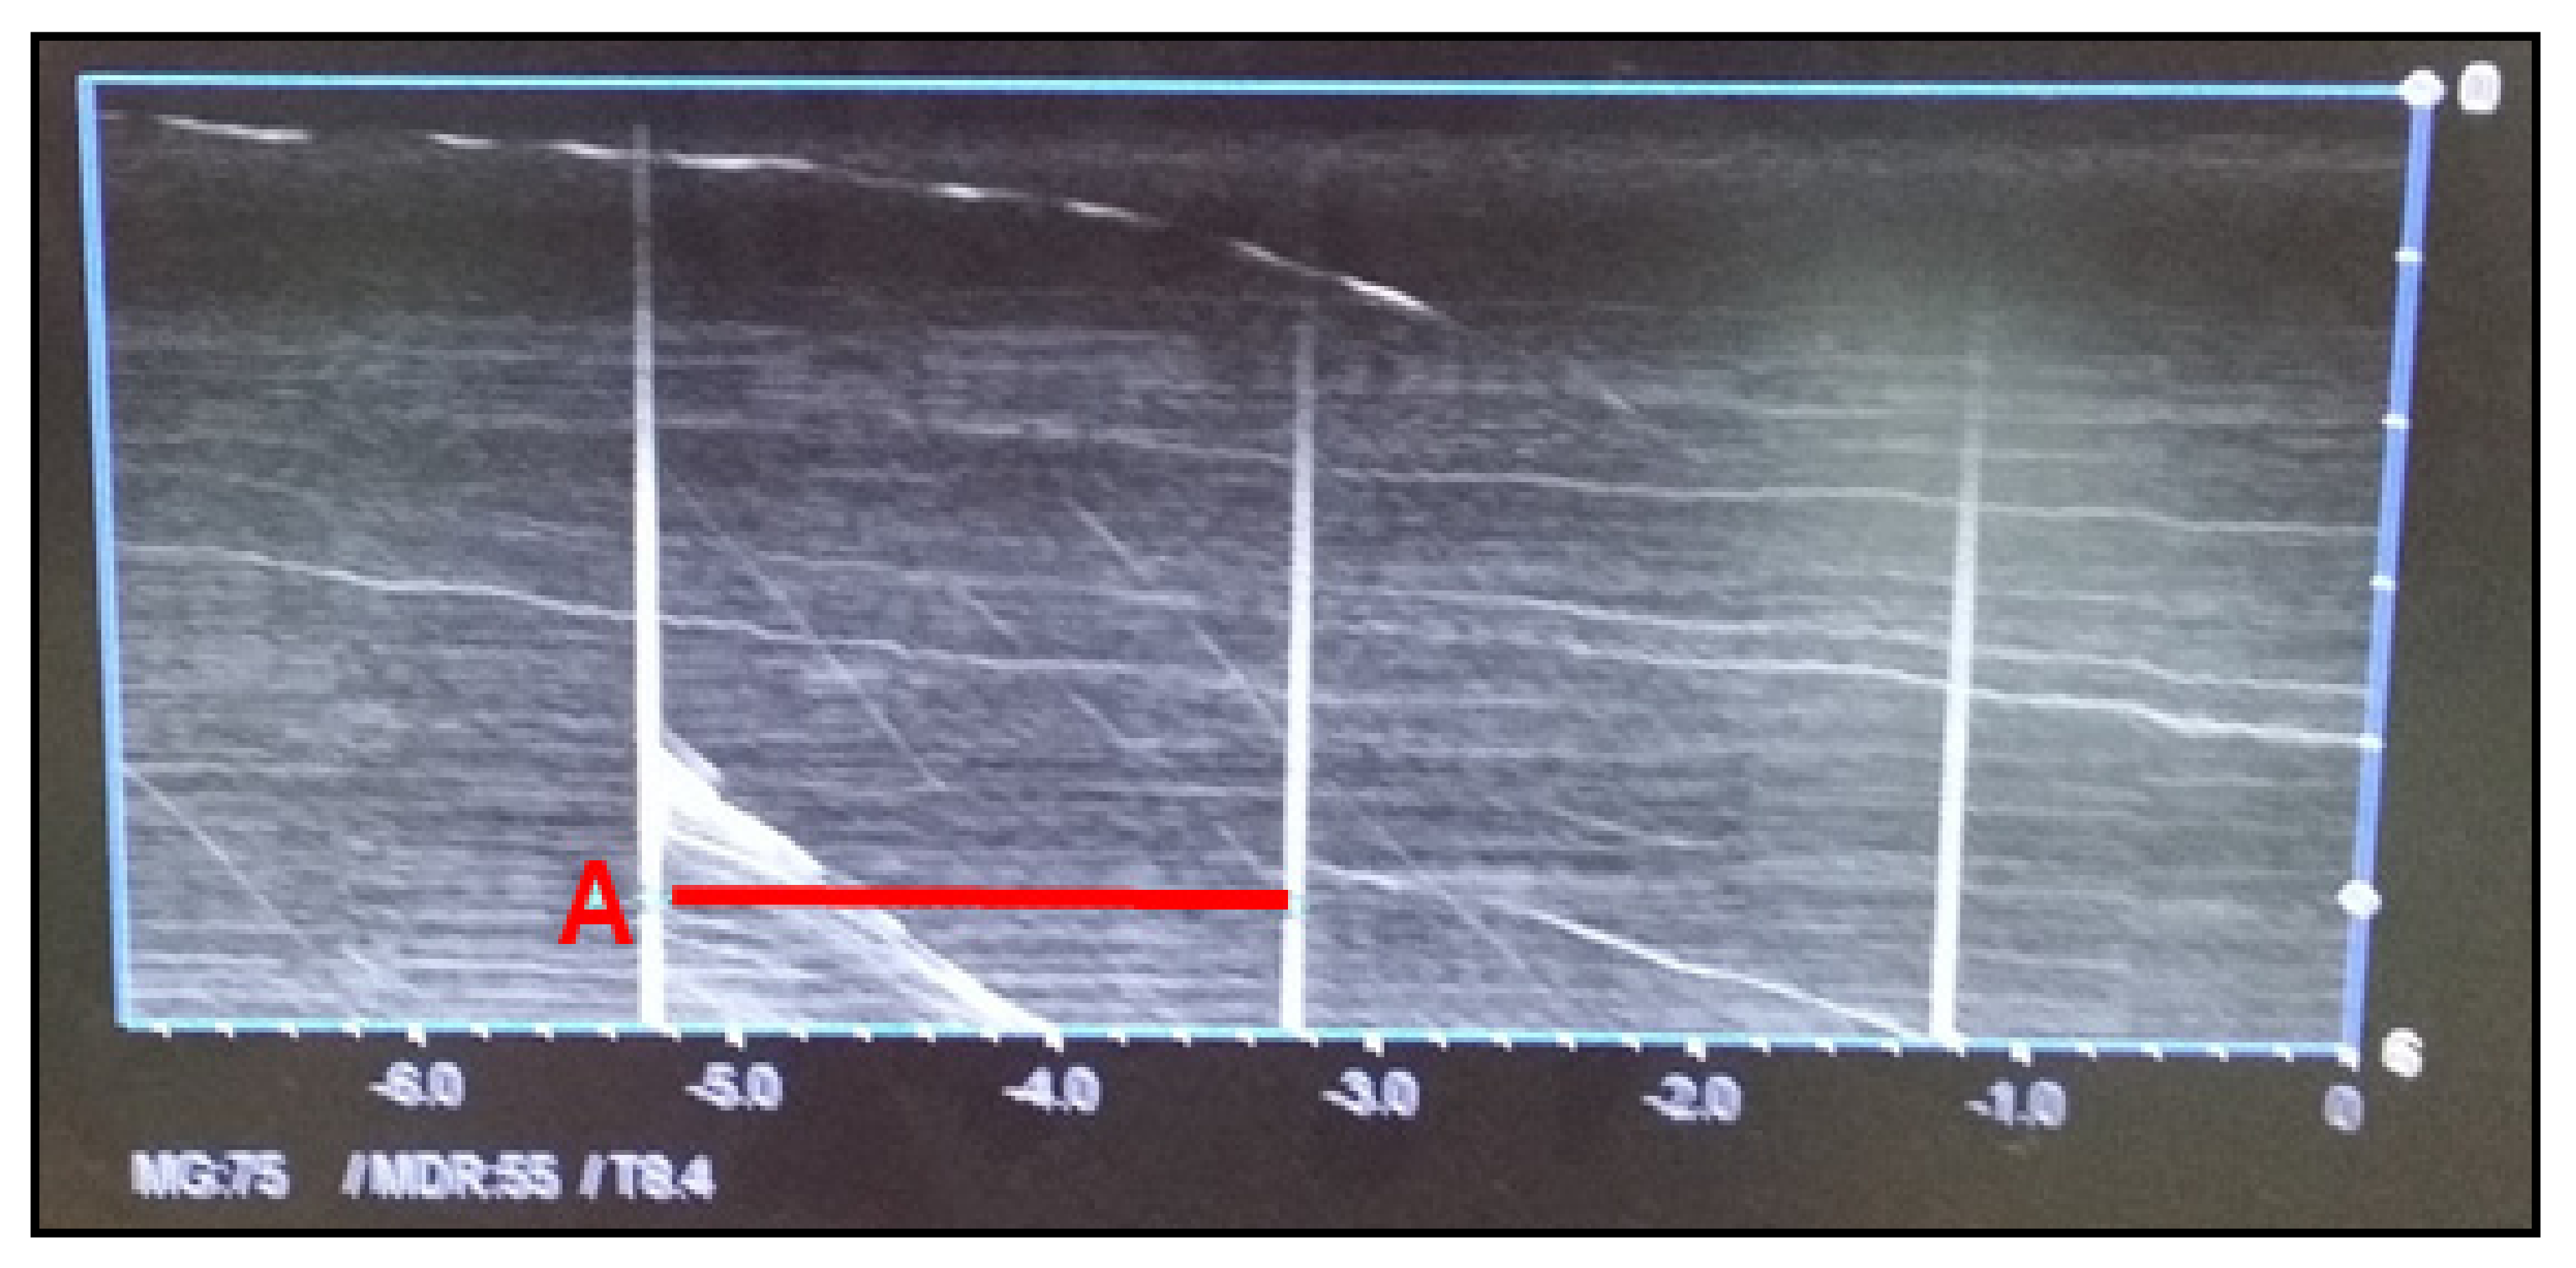

3.1.6. Time Accuracy Test

The time accuracy test is performed when the abdominal ultrasound has the M-mode function. The time accuracy test aims to test the accuracy of periodic ultrasound signals generated by the device. The vertical axis indicates frequency amplitude, whereas the horizontal axis indicates the time (s). The frequency period should be within ± 3% of the reference value. As shown in Figure 6, time is measured periodically every 2 s. The reference value for the period is 0.5 Hz, and it was 1/2 = 0.5 Hz in our test, which satisfied the reference value range.

Figure 6. Time accuracy.